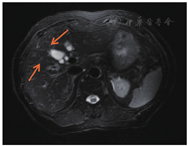

术后在外院行8个周期FOLFOX化疗(奥沙利铂85 mg/m2,ivgtt+氟尿嘧啶280 mg/m2,iv bolus+氟尿嘧啶1.4 g/m2,civ+亚叶酸钙280 mg/m2,ivgtt),2012年07月我院肝脏增强磁共振成像检查提示:肝多发转移瘤(图1)。